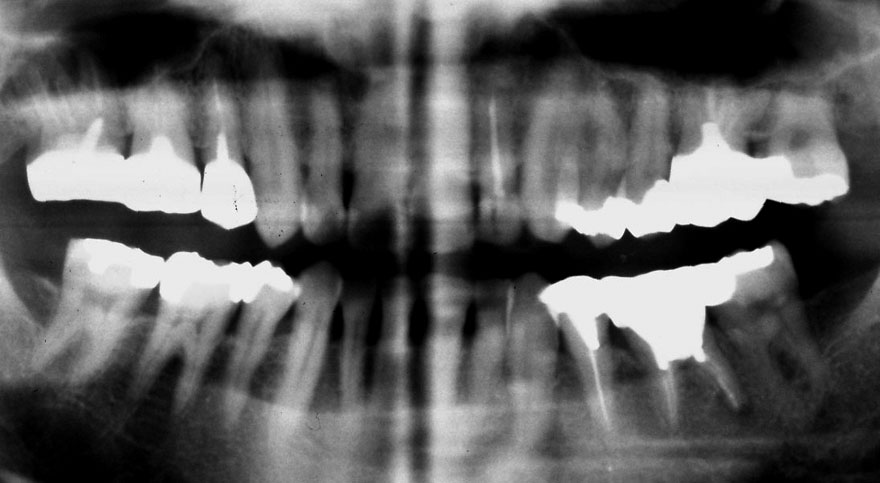

初診時 28歳 男性 平均歯槽骨喪失量:2.35mm

河田歯科医院

30年後 58歳

平均歯槽骨喪失量:3.88mm

22年間喪失量:-1.53mm

年間喪失速度:-0.05mm

(ケア頻度:2.80ヵ月ごと)

初診時 28歳 女性 平均歯槽骨喪失量:1.82mm

20年後 48歳

平均歯槽骨喪失量:2.60mm

20年間喪失量:-0.77mm

年間喪失速度:-0.04mm

(ケア頻度:1.36ヵ月ごと)